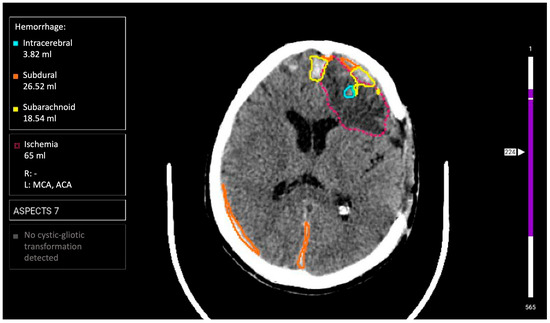

2.4. AI Services

3.1. Comparison of AI Services Among Themselves